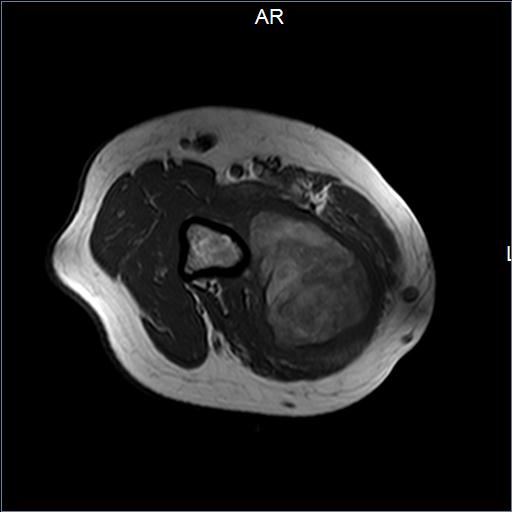

Mujer de 45 años con tumor en muslo derecho de lento crecimiento. Se realizó resección amplia de la lesión.

Lipoma condroide